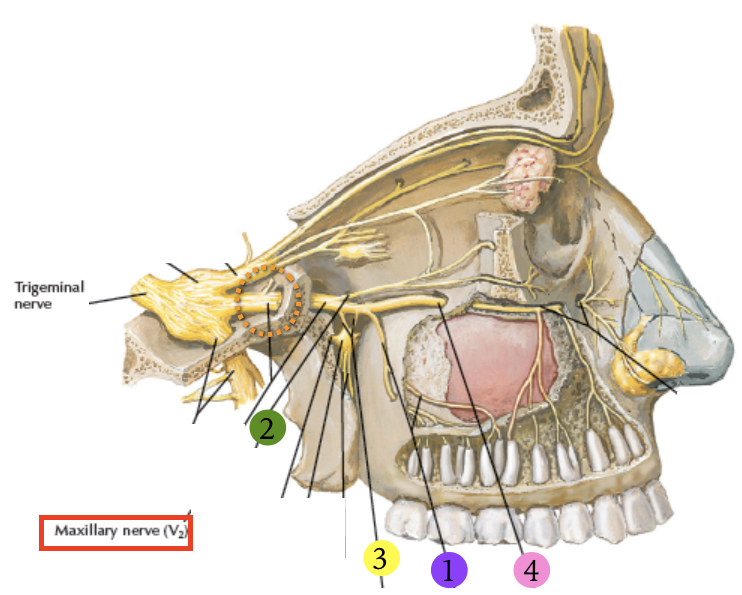

CN V2

Post. sup. alveolar n.

穿過 pterygomaxillary fissure,支配上顎臼齒(molars),除了第一大臼齒(mid. sup alveolar n.)

Warning

Infraorbital n.

感覺神經

- Ant./Mid sup. alveolar n.

- 與動脈伴行

- Sup. labial br.

- Nasal br.

Pterygopalatine ganglion